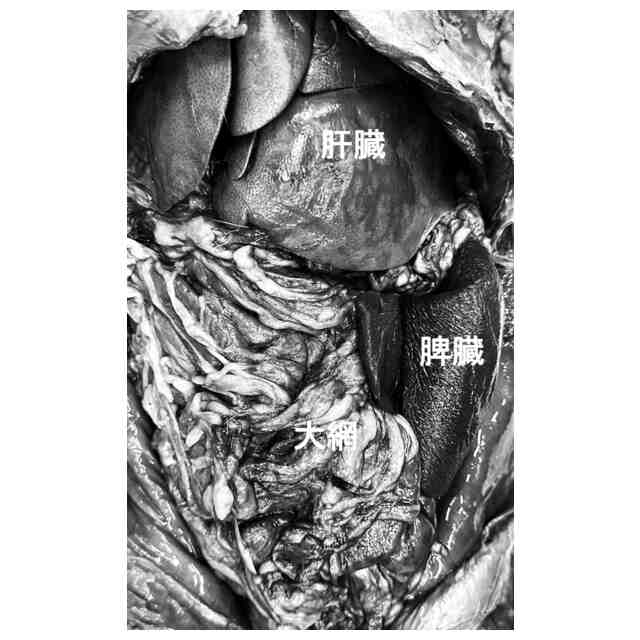

遺体に殺菌消毒・防腐等を行ったり修復したりして、遺体を衛生保全するとともに長期保存するための技術としてエンバーミングが知られている。このエンバーミング技術は、上述した人だけではなく、ペット等にも使用されている他、人体標本や動物標本等にも使用されている。

エンバーミング技術の一例として特許文献1に記載の遺体の固定方法がある。特許文献1では、遺体の食道、腹腔内、胸腔内および下顎周辺の少なくとも4箇所に遺体固定液を注入する。この遺体固定液として、少なくとも1種の脂肪族アルデヒドと、少なくとも1種の低級アルカノールと、水とを必須成分として含有する固定液が挙げられている。